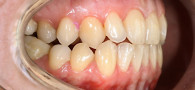

Улыбка после исправления прикуса

В клинику «Виртуоз» обратилась пациентка с жалобами на неудовлетворённость улыбкой из-за неровного расположения зубов.

После консультации и диагностики врач-ортодонт Ваге Гагикович предложил ортодонтическое лечение берекетами Damon Clear 2 (вч) и Damon Q2 на 4.4, 4.5, 3.4, 3.5.

Ортодонтическое лечение включало в себя установку брекет-систем, наблюдение врача и корректировку брекет систем по мере исправления прикуса. После окончания лечения пациентка два месяца носила ортодонтическую капу для закрепления результата. В итоге она получила ровную и красивую улыбку.